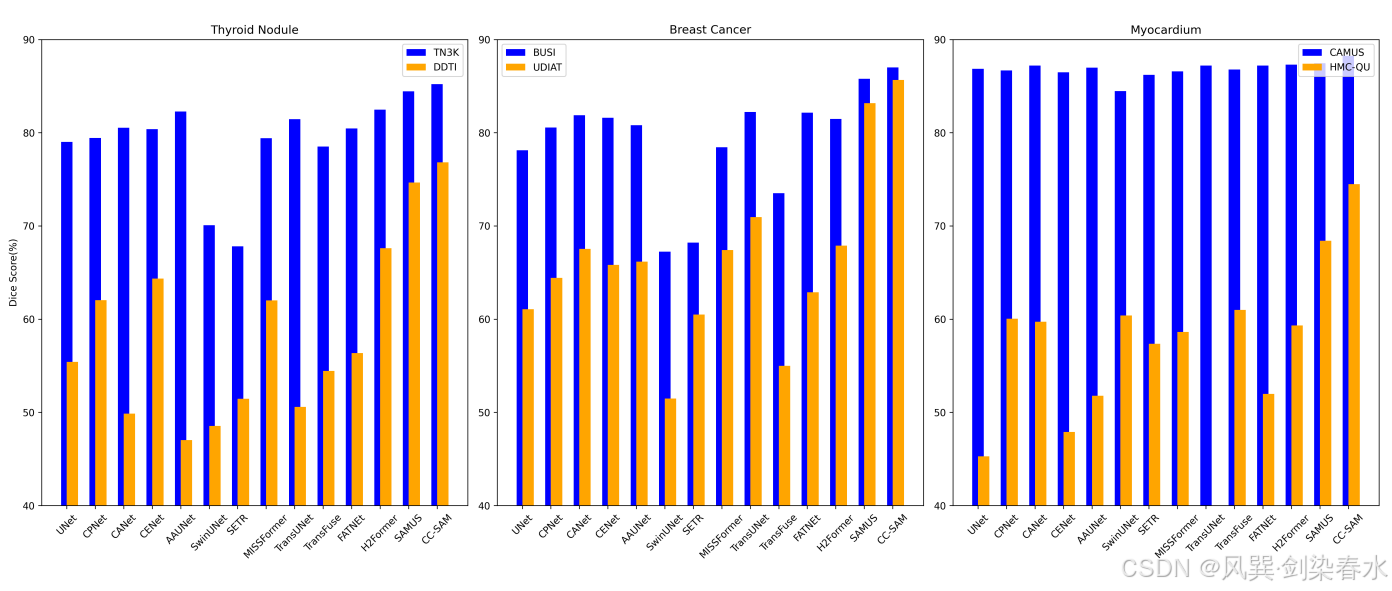

Figure 5 | CC-SAM 在可以看到的数据集(用蓝色高亮显示)和以前没有遇到过的未见数据集(用橙色表示)上与特定任务 SOTA 技术进行比较:橙色条越高,表示泛化能力越强。